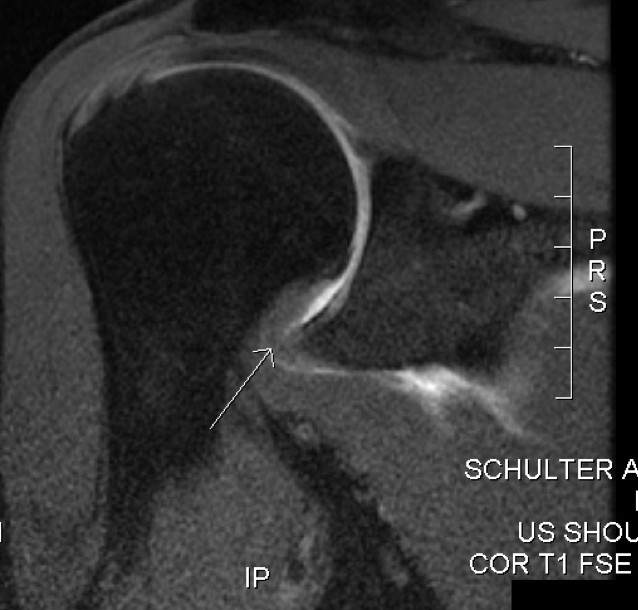

From radiopaedia.org

Adhesive capsulitis shoulder Image Adhesive Capsulitis Examples Adhesive capsulitis (also known as frozen shoulder) is a condition of the shoulder characterized by functional loss of both passive and active shoulder motion commonly. Adhesive capsulitis (ac) is characterized by fibrosis and contracture of the glenohumeral joint capsule, resulting in. Frozen shoulder, often referred to as adhesive capsulitis (ac), is characterized by initially painful and later progressively restricted active. Adhesive Capsulitis Examples.